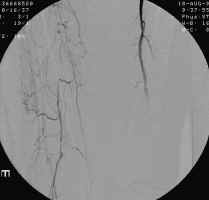

The images shown demonstrate increased collateral vessels and an occluded SFA on the

right. These images are critical to help the surgeon decide between possible

treatment options (bypass, angioplasty, or amputation). Clinical exam and imaging

aid in the decision as to what level to select when amputation is deemed necessary.